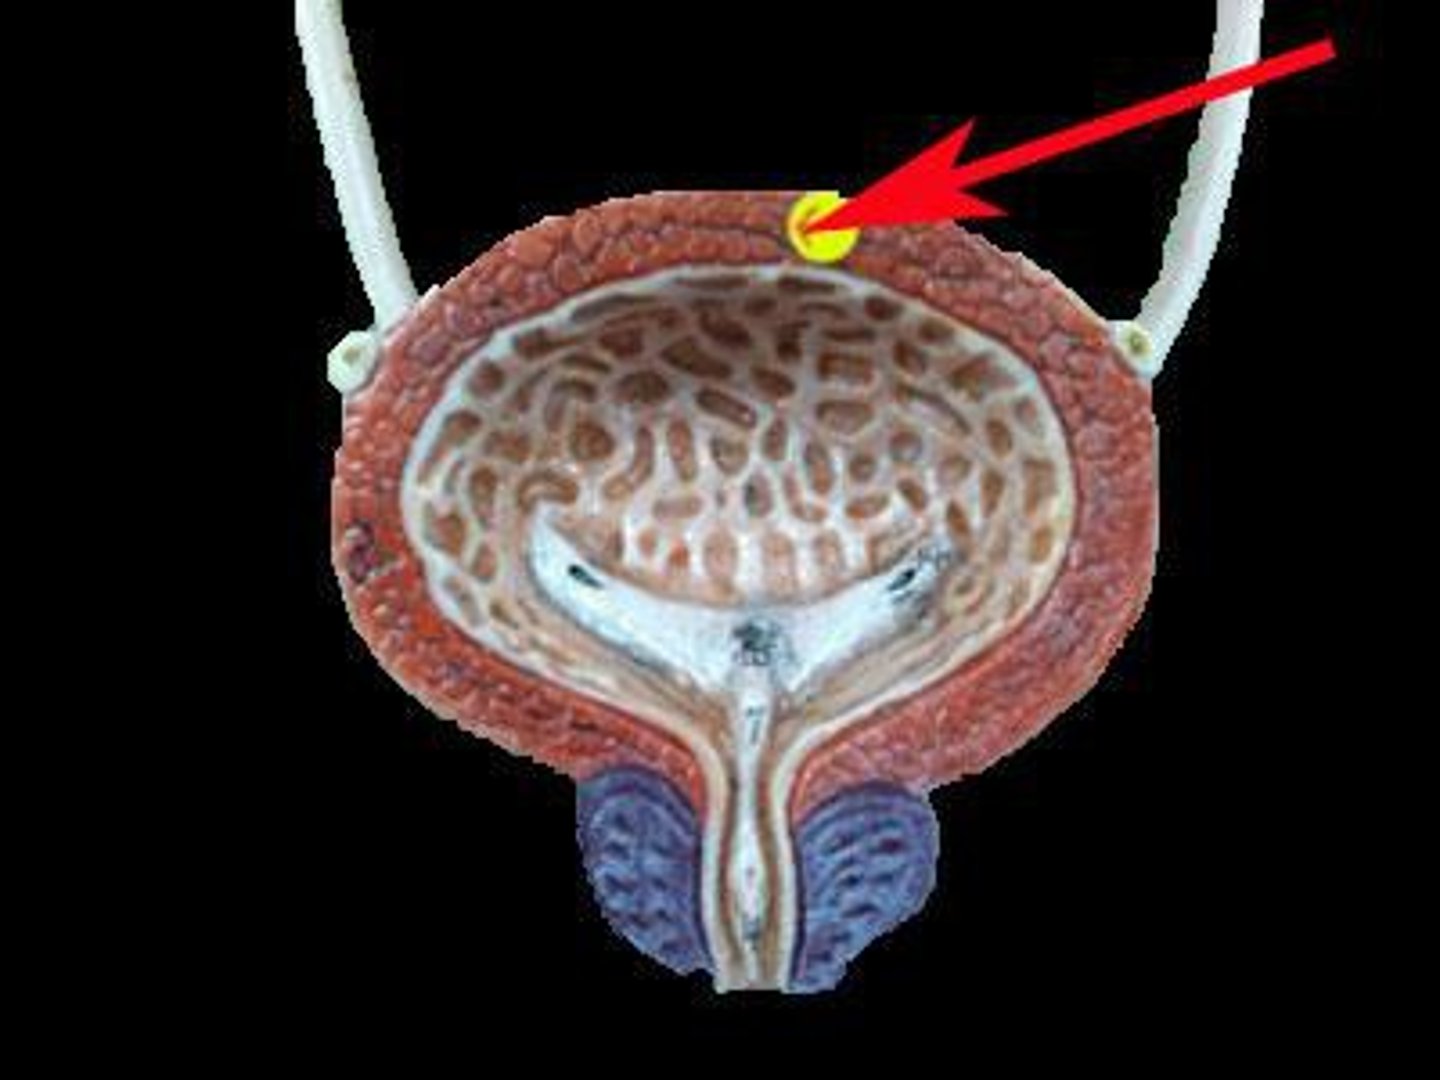

urinary bladder

hollow, muscular sac that holds and stores urine lined with transitional epithelial cells

detrusor muscle

Smooth muscle that compresses the urinary bladder and expels urine into the urethra.

internal urethral sphincters

involuntary and made of smooth muscle

external urethral sphincters

Voluntary and made of skeletal muscle